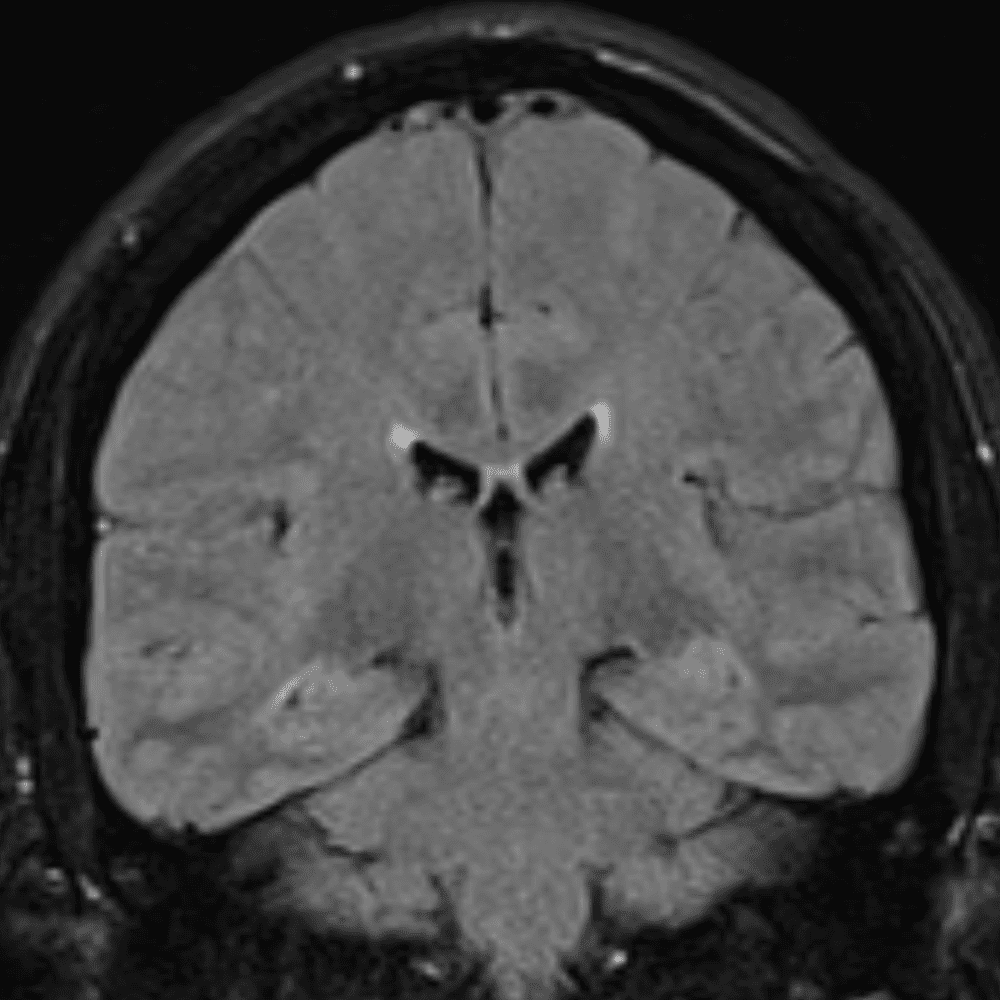

๋‹น์ง ์‹œ ํ”ํžˆ ๋ณผ ์ˆ˜ ์žˆ๋Š” ์‚ฌ๋ก€์˜ ์ „ํ˜•์ ์ธ ์˜ˆ๋ฅผ ํฌํ•จํ•ฉ๋‹ˆ๋‹ค.

39 ์‚ฌ๋ก€

์—ฐ์Šต

๋ฏธ๋ฌ˜ํ•˜๊ฑฐ๋‚˜ ์–ด๋ ค์šด ์‚ฌ๋ก€์™€ ์ผ๋ถ€ ์ •์ƒ ์‚ฌ๋ก€๋ฅผ ํฌํ•จํ•˜์—ฌ ๋‹น์ง์„ ์‹œ๋ฎฌ๋ ˆ์ด์…˜ํ•ฉ๋‹ˆ๋‹ค.

50 ์‚ฌ๋ก€